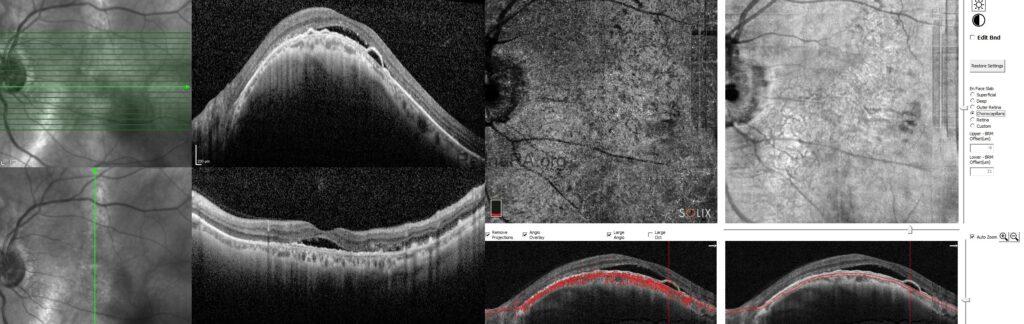

Vertical and horizontal OCT scans of the left eye demonstrated dome-shaped macular configuration with subretinal fluid in addition to shallow pigment epithelial detachment overlying the dome shape.

To rule-out the accompanying macular neovascularization, OCT-A was performed and any neovascular membrane could not detected.